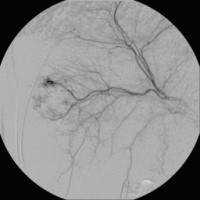

Superselektive transarterielle Chemoembolisation (TACE) mit Sondierung eines tumorversorgenden Gefäßes 3

(Bild 5 von 5)